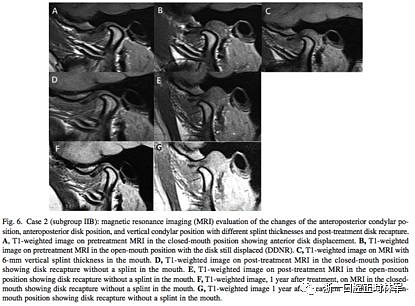

在治療12個(gè)月后,IIB組中有7例關(guān)節(jié)盤完全復(fù)位,而IIA組0例。在這7例中,張閉口位關(guān)節(jié)盤均復(fù)位的只有3例,其余4例只有在張口位時(shí)復(fù)位了(即從DDNR轉(zhuǎn)變?yōu)镈DR,分別見圖5和圖6)。再過一年后,對(duì)這7例進(jìn)行MRI研究,發(fā)現(xiàn)關(guān)節(jié)盤保持于其復(fù)位的位置。